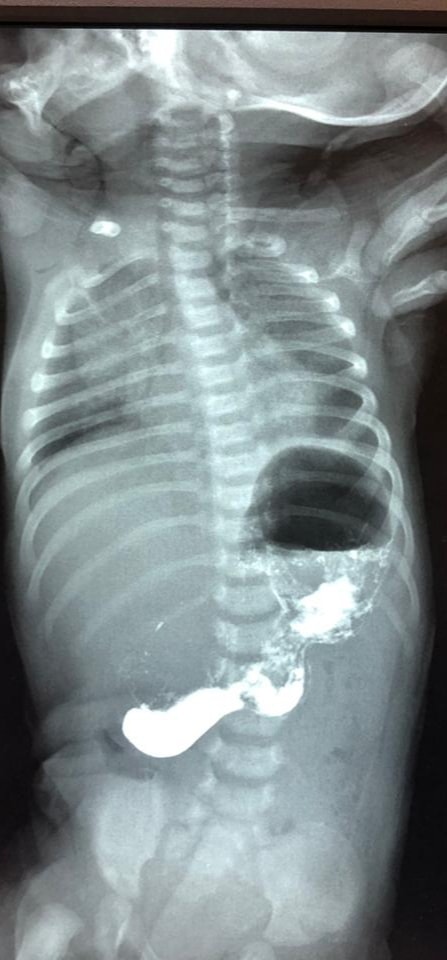

Medicina.az xəbər verir ki, əməliyyat 40 günlük körpə üzərində həyata keçirilib.Körpə 3 gündür dayanmadan qusduğu üçün xəstəxanaya gətirilib.

Müayinə nəticəsində məlum olub ki, qusmanın səbəbi mədə çıxışında olan daralma,əzələ qalınlaşmasıdır. Buna görə də 40 günlük uşağa cərrahi müdaxilə qərarı verilib.

Lakin əməliyyat riskli olduğu üçün, 1 gün ərzində onun ümumi vəziyyətini yaxşılaşdırmaq üçün müalicələr aparılıb. Daha sonra baş tutan əməliyyat uğurlu keçib. Körpənin mədə çıxışında qidanın keçməsinə mane olan qalınlaşmış əzələ qatı kəsilib.